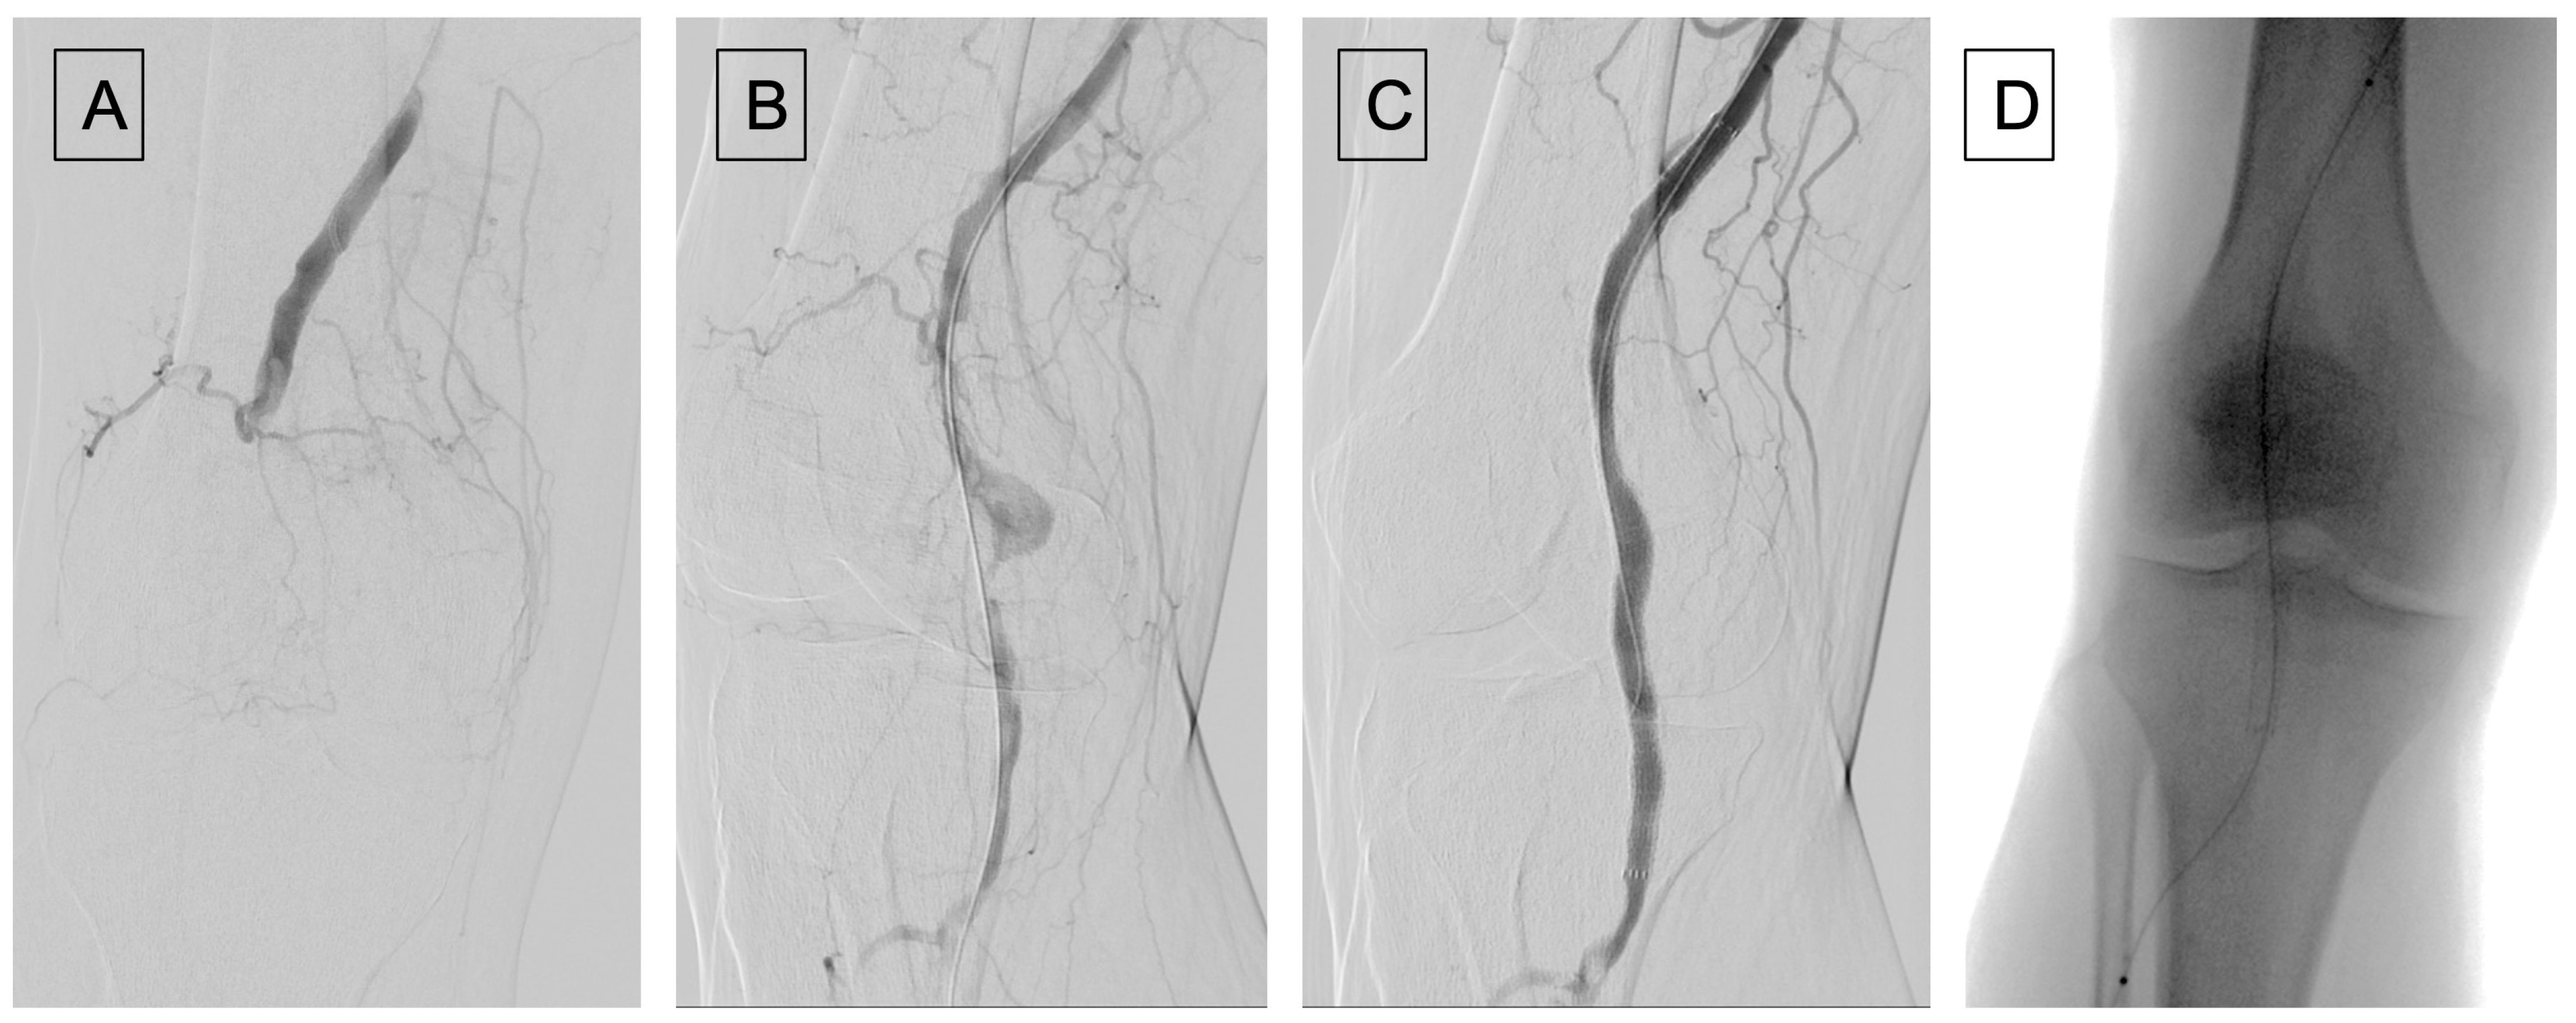

Figure 2.

(A) Angiography showing a popliteal artery aneurysm thrombosis; (B) after recanalization using a thrombo-embolectomy system (Indigo catheter from Penumbra); (C) angiographic control after Viabahn placement, pointing out a distal popliteal residual non occlusive thrombosis. (D) Placement of Cragg-McNamara catheter for local fibrinolysis.